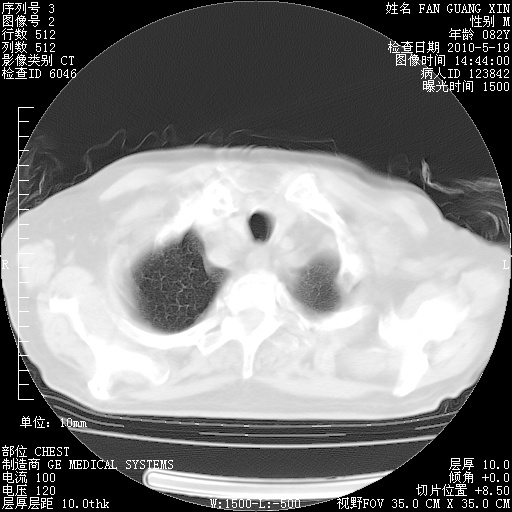

可改为口服强的松40-50mg/d治疗,若病情仍稳定,胸部阴影不再吸收可逐渐减量